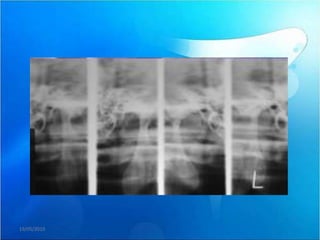

Diagnostico

PANORAMICA

RX

RESONANCIA ARTICULAR

MAGNETICA

TOMOGRAFIA

COMPUTARIZADA